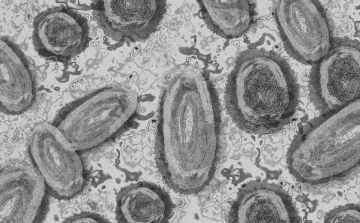

Még több hónapon át folytatódik a majomhimlő elleni oltási kampány Franciaországban

Franciaországban még több hónapon át folytatódik a majomhimlő elleni oltási kampány 2022-ben és várhatóan 2023 elején is, miután az általános megelőzés következtében most először csökkeni kezdtek a mutatók

Tovább nőtt a majomhimlő-fertőzöttek száma Magyarországon

Újabb két embernél igazolt majomhimlő-fertőzést a Nemzeti Népegészségügyi Központ (NNK) a 33. héten - augusztus 15-től 21-ig -, ezzel 64-re nőtt a magyarországi esetek száma.